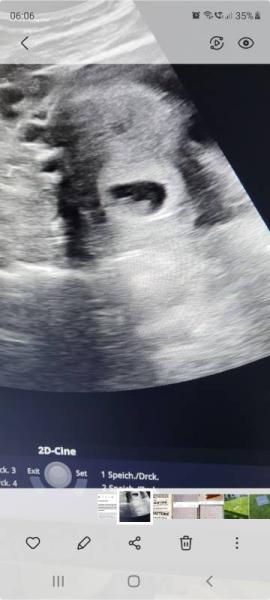

Antwort auf Beitrag von Sina00

Das war 12 Tage später

Bild zu